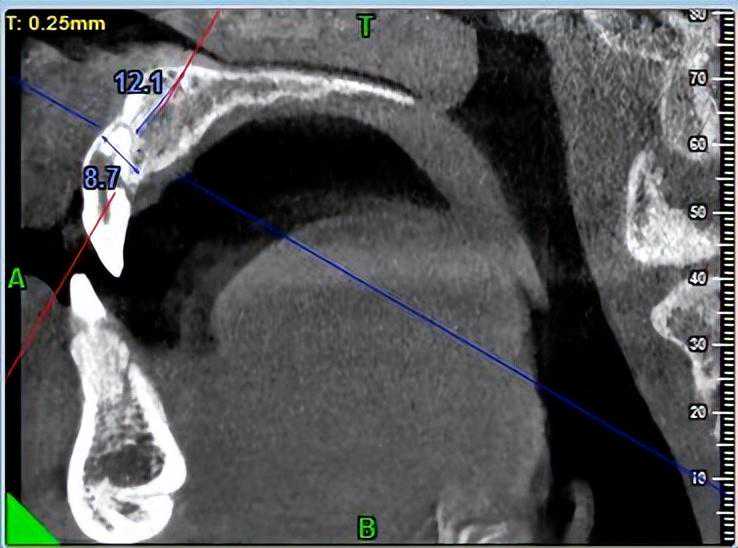

a的服务很好,洗牙过程不停安微告知,服务的很到位。我有个牙齿小学摔裂了1/4,当时补过的。洗牙医生看到我牙龈处有一颗小息肉,建议我拍个X照片来看看什么情况。得知是免费的,我马上同意了。医生放下手上工作,带我去拍照,特意吩咐护士先让我拍。很快拿到结果,医生带我去院长这。院长告诉我,我的牙齿之前摔过的,做的填充不好,里面已经发炎了,牙齿根部已经很溃败了,要把牙齿拔了重新种植。给了我韩国进口牙和美国进口牙的价格,大概8k左右就能包一切。大概流程是,先拔牙,空着半年后再种牙。

刚开始接触,也是让我拍牙齿X照。完了很耐心的给我分析,还有之前的方案,给出治疗的方法,起码我听起来很专业,也深感同受。到现在为止我去了有10次了,每次都是治疗,有几次都是超过1.5小时的,虽然开口时间久很累,但是医生也任劳任怨。目前息肉没有切,通过治疗是慢慢消除了。过多一个礼拜就可以彻底的搞定了。